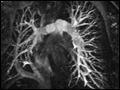

| Figure 229-16 MRA scan of a patient with partial anomalous pulmonary venous drainage of the right lung into the inferior vena cava (scimitar syndrome). MRA is able to define the abnormal anatomic relationships of cardiac structures and great vessels in patients with congenital heart disease. | |

view large |